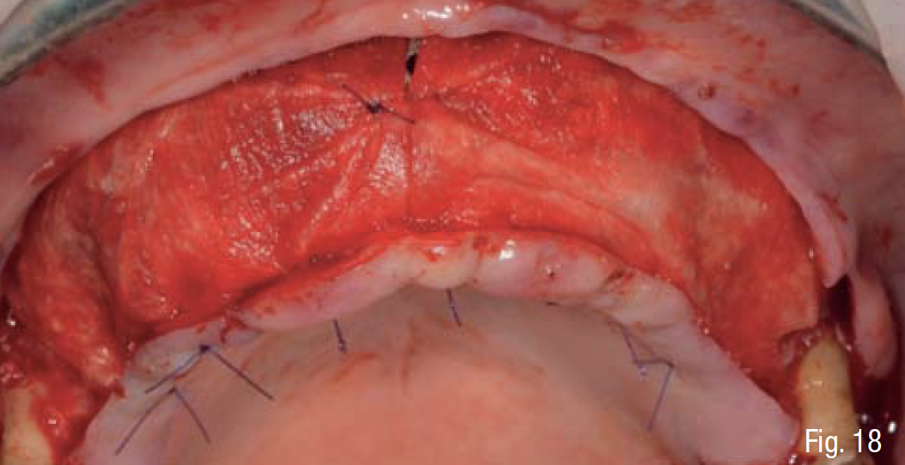

Infine, è stata eseguita un’attenta chiusura di prima intenzione dei lembi chirurgici, mediante una sutura a doppio strato, costituita da una linea di punti a materassaio orizzontale e da una linea di punti staccati singoli, per garantire una chiusura ermetica della ferita (SERAFAST 5/0, Serag-Wiessner, Naila, Germany) (Figg. 18, 19). Nei 7 giorni consecutivi il paziente ha proseguito la terapia antibiotica a base di amoxicillina e acido clavulanico e una terapia antiinfiammatoria a base di nimesulide; risciacqui con clorexidina 0.20% 3 volte al giorno per 2 settimane; e non ha utilizzato la protesi parziale rimovibile sempre per 2 settimane. Dopo 9 mesi, essendo stata confermata una sufficiente mineralizzazione del volume osseo al di sotto della griglia mediante una CBCT post-operatoria (Figg. 20-22), è stata pianificata una chirurgia computer-guidata per inserire gli impianti in modo protesicamente guidato (Figg. 23, 24).